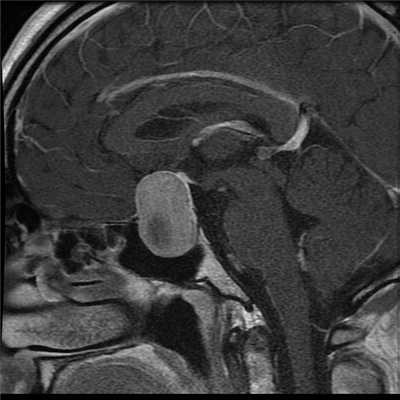

Киста кармана Ратке на МРТ

- киста кармана Ратке;

- краниофарингиома;

- арахноидальная киста.

МРТ гипофиза - киста кармана Ратке

Киста — это полое новообразование, заполненное жидкостью. Она носит доброкачественный характер и редко увеличивается в размерах. Самой распространенной формой кист гипофиза является киста кармана Ратке - образование, развивающееся между двумя долями гипофиза у основания головного мозга. Чаще всего киста кармана Ратке образуется во время эмбриологического развития из предшественника гипофиза. Диагностика данного кистозного образования возможна с помощью МРТ гипофиза. Признаками кисты Ратке на МРТ будет:

- на нативных изображениях между нейро- и аденогипофизом определяется зона измененного МР-сигнала с ровными четкими контурами, гипоинтенсивного МР-сигнала на Т1-ВИ, гиперинтенсивного на Т2-ВИ.